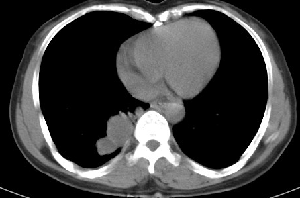

下叶后基底段近膈面见一椭圆形密度均匀增高的阴影,边界较清,其长轴指向内后方,考虑肺隔离症,建议增强扫描了解与主a联系!

右下肺隔离症有可能,另外可能是炎性假瘤

右下肺隔离症可能性大,不除外炎性假瘤、神经原性肿瘤

三无产品!只能依影论影 :首先考虑炎症,建议抗炎治疗后复查

1.后纵隔神经原肿瘤,2.炎性假瘤。建议密切结合临床或抗炎治疗后复查。